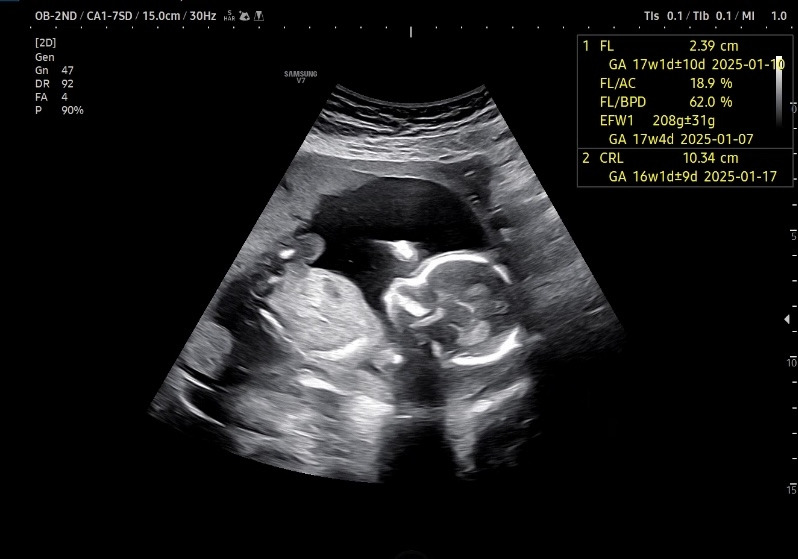

자궁 경부 길이도 좋고 주수에 맞게 건강히 잘 크고 있답니다.